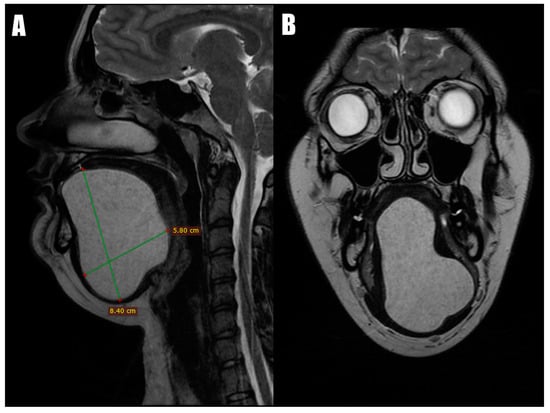

Magnetic Resonance Imaging (MRI) revealed a well-defined T1 hypointense cystic lesion and a T2 hyperintense cystic lesion located above the mylohyoid and geniohyoid muscles (Figure 2). The base of the tongue was slightly displaced, leading to a narrowing of the upper airway passage. The cystic lesion extended from the submental area to the floor of the mouth and superiorly into the tongue, measuring 5.8 × 8.4 cm at its largest dimensions. A fine-needle aspiration cytology (FNAC) revealed a dense, mud-like content with keratin and anucleated squamous cells without any signs of inflammation, suggesting the diagnosis of a dermoid cyst. Following this diagnosis, the patient was promptly scheduled for surgical intervention.

Figure 2.

MRI scans: the coronal view (A) and the axial view (B) demonstrate that the submental and sublingual dermoid cyst extended superiorly, dividing intrinsic tongue muscles.